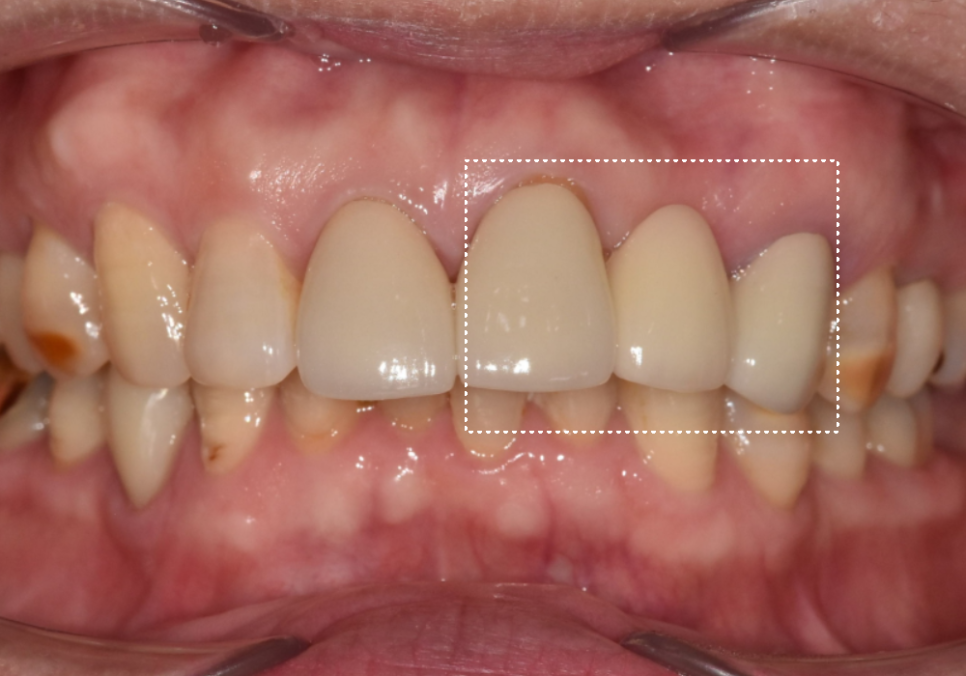

입안을 살펴보니 겉보기에는

큰 문제가 없어 보였지만,

유독 송곳니 부위(#23)의 잇몸 색이 거뭇하고

부어있는 상태였어요.

어떠세요? 주변 치아와 조화를 이루며

아주 자연스럽게 마무리된 모습이죠?

단순히 심는 것에 그치지 않고

뼈 상태, 잇몸 회복,그리고 정교한 교합까지

세밀하게 고려하여 자연스러운 보철이

완성되었습니다.^^